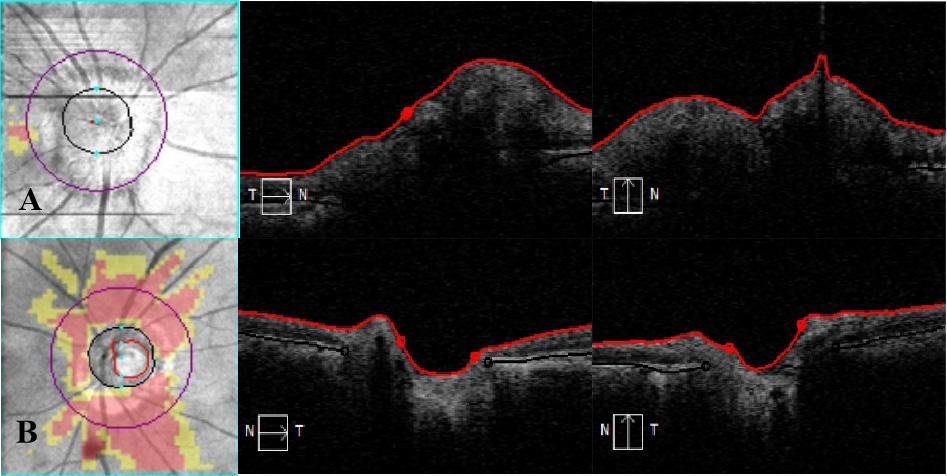

20230327090314_0199.png

图 4 视盘 OCT

Figure 4 OCT examination of the optic disc

右眼视盘视神经纤维层水肿、增厚,左眼视盘视神经纤维层萎缩、变薄。

It showed edema and thickening of the optic nerve fiber layer in the right eye and atrophy and thinning of the optic nerve fiber layer in the left eye.

20230327090505_8516.png

图 5 黄斑 OCT

Figure 5 OCT examination of the macula

双眼黄斑区视网膜形态正常,层间未见异常信号。

It showed the morphology of retina in macular region of both eyes is normal, and no abnormal signal is found between layers.